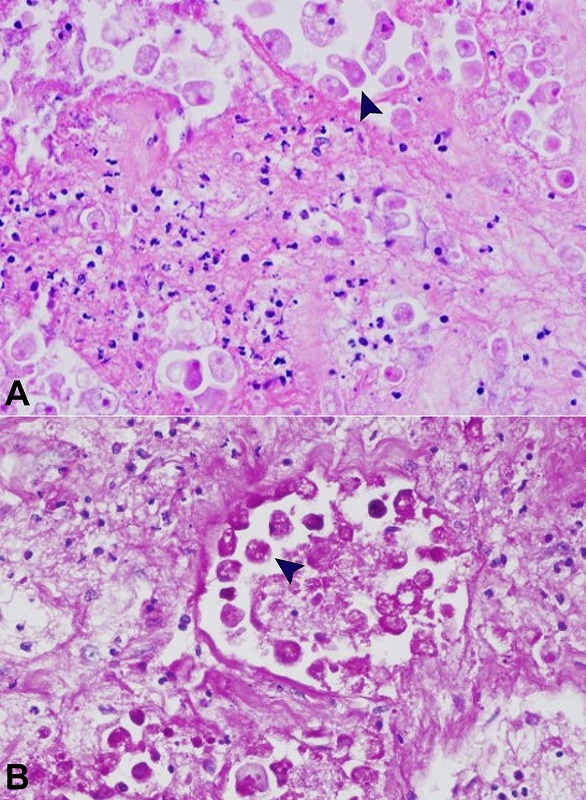

An intestinal perforation was observed in the right colon together with local acute suppurative peritonitis. Histologically, the ulcers were deep, extending into the submucosa and undermining borders. The lesions comprised necrotic material with prominent nuclear debris and few inflammatory cells. Amebic trophozoites were found at the ulcers’ edges, together with mild mononuclear inflammation (Figure 2A). Amebic trophozoites had a foamy cytoplasm with round eccentric nuclei resembling large macrophages. Red blood cells were phagocytized by the trophozoites, which were stained by Periodic Acid-Schiff (PAS) (Figure 2B). There was no hepatic, pulmonary, or other extra-intestinal involvement. Death was attributed to sepsis from the intestinal lesions.

In the current case, many ulcers were found in the colon. They were geographic and necrotizing, measuring between five and two centimeters and extending from the cecum to the rectum. The histological examination showed an extension of the necrosis and inflammation to the muscular layers in many areas. The involvement of the whole large intestine, as observed in the present case, is sporadic and associated with high mortality.10,25 The microscopic examination was crucial to disclose the infectious etiology by showing round organisms with 20-30 mm and intracytoplasmic erythrocytes at the ulcers’ edge, recognized as amebic trophozoites, confirming the diagnosis of invasive amebiasis. Although the three species of the entamoeba complex: Entamoeba histolytica, Entamoeba dispar, and Entamoeba moshkovskii, cannot be distinguished by morphology, the context of the lesions in the present case are highly suggestive of Entamoeba hystolytica as the etiologic agent. However, it should be pointed out that under certain circumstances, the “avirulent” species of Entamoeba díspar and Entamoeba moshkovskii can become pathogenic and cause disease.26-28

It is also essential to consider that Entamoeba’s morphologic features may mimic tissue macrophages or ganglion cells, and the diagnosis may be missed if the pathologist is unaware of this resemblance. Ancillary tests like Periodic-acid Schiff (PAS) stain or immunohistochemistry can be used to depict Entamoeba cysts and/or trophozoites in the lesions.11,33